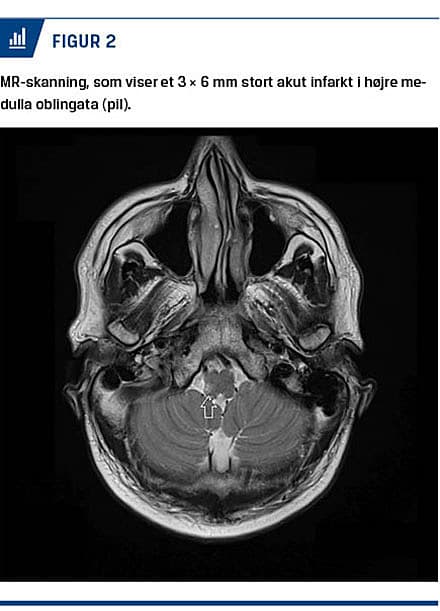

En 35-årig mand med insulinkrævende diabetes type 1 blev henvist fra en regional akutafdeling til en praktiserende speciallæge i øre-næse-hals-sygdomme mhp. videre behandling på mistanke om neuritis vestibularis (NV). Forud for henvisningen blev der udført akut CT af cerebrum uden patologiske fund. På henvisningstidspunktet havde patienten haft tre dage med pludseligt opstået svimmelhed, kvalme, opkastninger, hovedpine og gangbesvær uden neurologisk deficit. Hos øre-næse-hals-lægen blev der foretaget øre-næse-hals-undersøgelse, neurootologisk undersøgelse samt vHIT og videonystagmografi (VNG). Under den neurootologiske undersøgelse fandt man positiv Rombergs test med faldtendens til højre side, men normalt resultat ved en skew deviation test. VNG viste en spontan horisontal-tortional venstrerettet nystagmus (hastighed > 6° pr. s), som var uændret ved skift af blikretning. Patienten kunne fiksere og dermed undertrykke spontannystagmus. Resultatet af vHIT var normalt, dvs. uden asymmetrisk gain eller kompensatoriske overt og covert saccades (Figur 1). Efter forslag fra en neurootolog blev patienten henvist til MR-skanning på mistanke om hjernestammeinfarkt. MR-skanningen viste et akut infarkt

i højre medulla oblingata på 3 × 6 mm (Figur 2), og patienten blev herpå henvist til neurologisk relevant behandling. Han kom sig efterfølgende godt over sin tilstand.